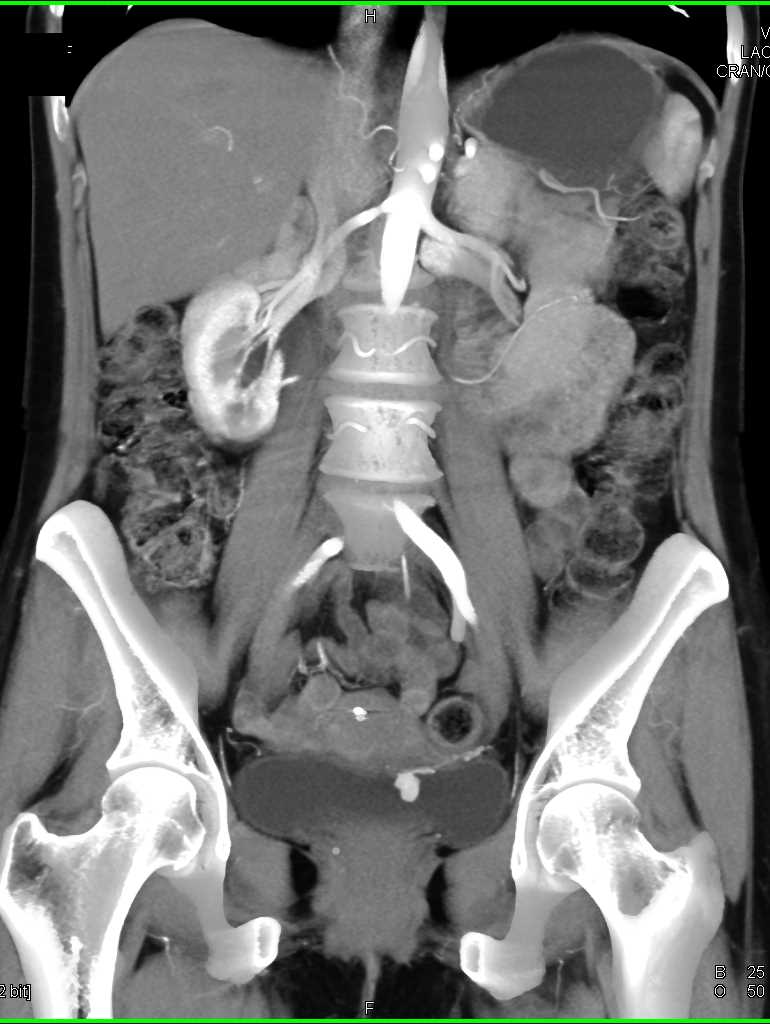

Bladder Cancer with Active Bleed